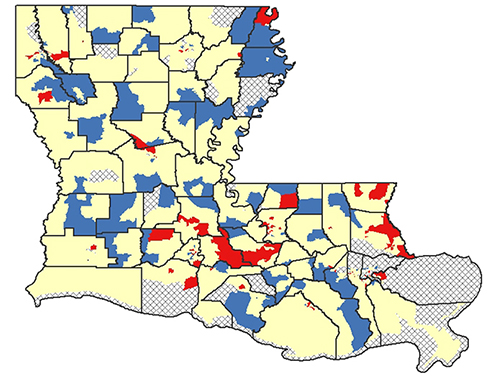

LSU Health New Orleans LA Tumor Registry Releases 6th Census Tract Cancer Incidence Report

LSU Health New Orleans Louisiana Tumor Registry (LTR) has published the sixth report of statewide cancer incidence rates by census tract. The publication, which reports 2010-2019 combined cancer incidence data, found that 81% of the census tracts in Louisiana met publication criteria for all cancers combined. More

LSU Health New Orleans LA Tumor Registry Releases 5th Census Tract Cancer Incidence Report

LSU Health New Orleans Louisiana Tumor Registry (LTR) has published the fifth report of statewide cancer incidence rates by census tract. The publication, which reports 2009-2018 combined cancer incidence data, found that 81% of the census tracts in Louisiana met publication criteria for all cancers combined. For specific cancer types, fewer census tracts met the criteria. For the Louisiana census tracts meeting the criteria, the incidence rates for all cancers combined and for specific cancer types were compared with the corresponding rates for the entire state. More